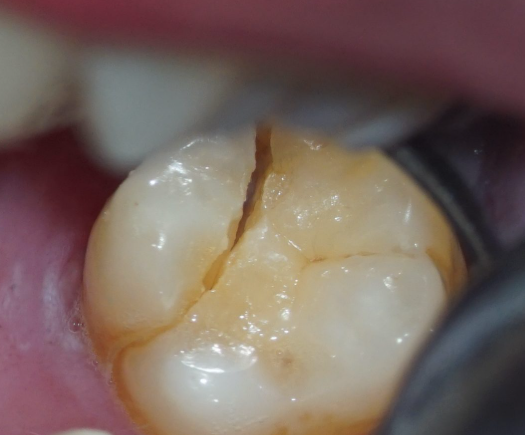

歯のヒビ(クラックトゥース)

■“歯のヒビ”が抜歯につながる?見えないトラブルの正体

歯のトラブルといえば「虫歯」や「歯周病」が代表格ですが、実は見落とされやすい厄介な問題があります。 それが「歯のヒビ」、いわゆるクラックトゥース症候群(Cracked Tooth Syndrome)です。

歯にヒビが入るというと、「割れた」や「欠けた」といった明らかな状態を想像されるかもしれません。 しかしクラックトゥースは、それよりもごく小さな“線状のひび割れ”のこと。 レントゲンにも映らないことが多く、患者さん自身も気づかないまま進行してしまうことがあるのです。

これらは虫歯や知覚過敏とも似ているため、患者さん自身が見分けるのは困難です。 しかもクラックトゥースはヒビの方向や深さによって症状が変わるため、歯科医師でも診断が難しいケースがあります。